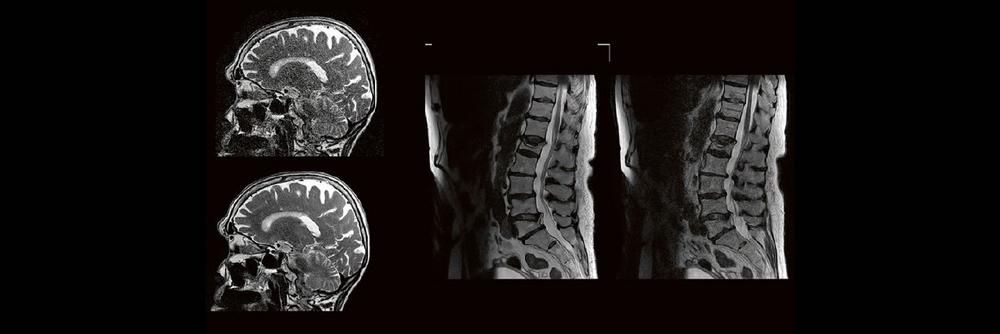

Professor Dr. med. Matthias PumbergerPD Dr. med. Torsten Diekhoff Die Dual-Energy-Computertomographie (DECT) hat für viele klinische Anwendungen bereits Einzug in…